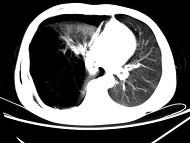

问题 男,32岁,被车撞伤后1小时,请结合影像图像选择其最可能的诊断为 ( )

选项 A.右侧气胸 B.右肺不张 C.右侧气胸并皮下纵隔气肿 D.右侧肺大疱并皮下纵隔气肿 E.支气管断裂

答案 C